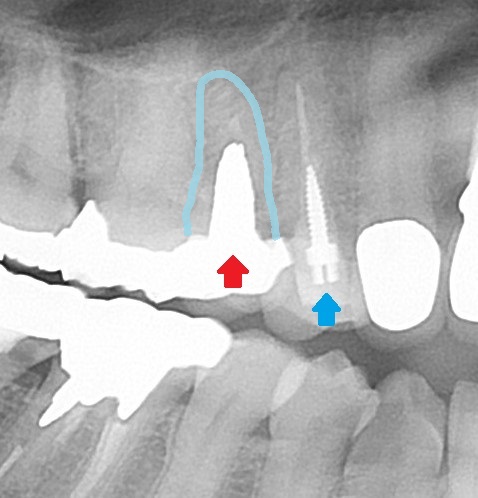

根管治療レントゲン

根の先まで清掃消毒を行い、お薬を入れて密閉しています。

後は、土台を立てて、クラウンをセットすると治療は終わります。